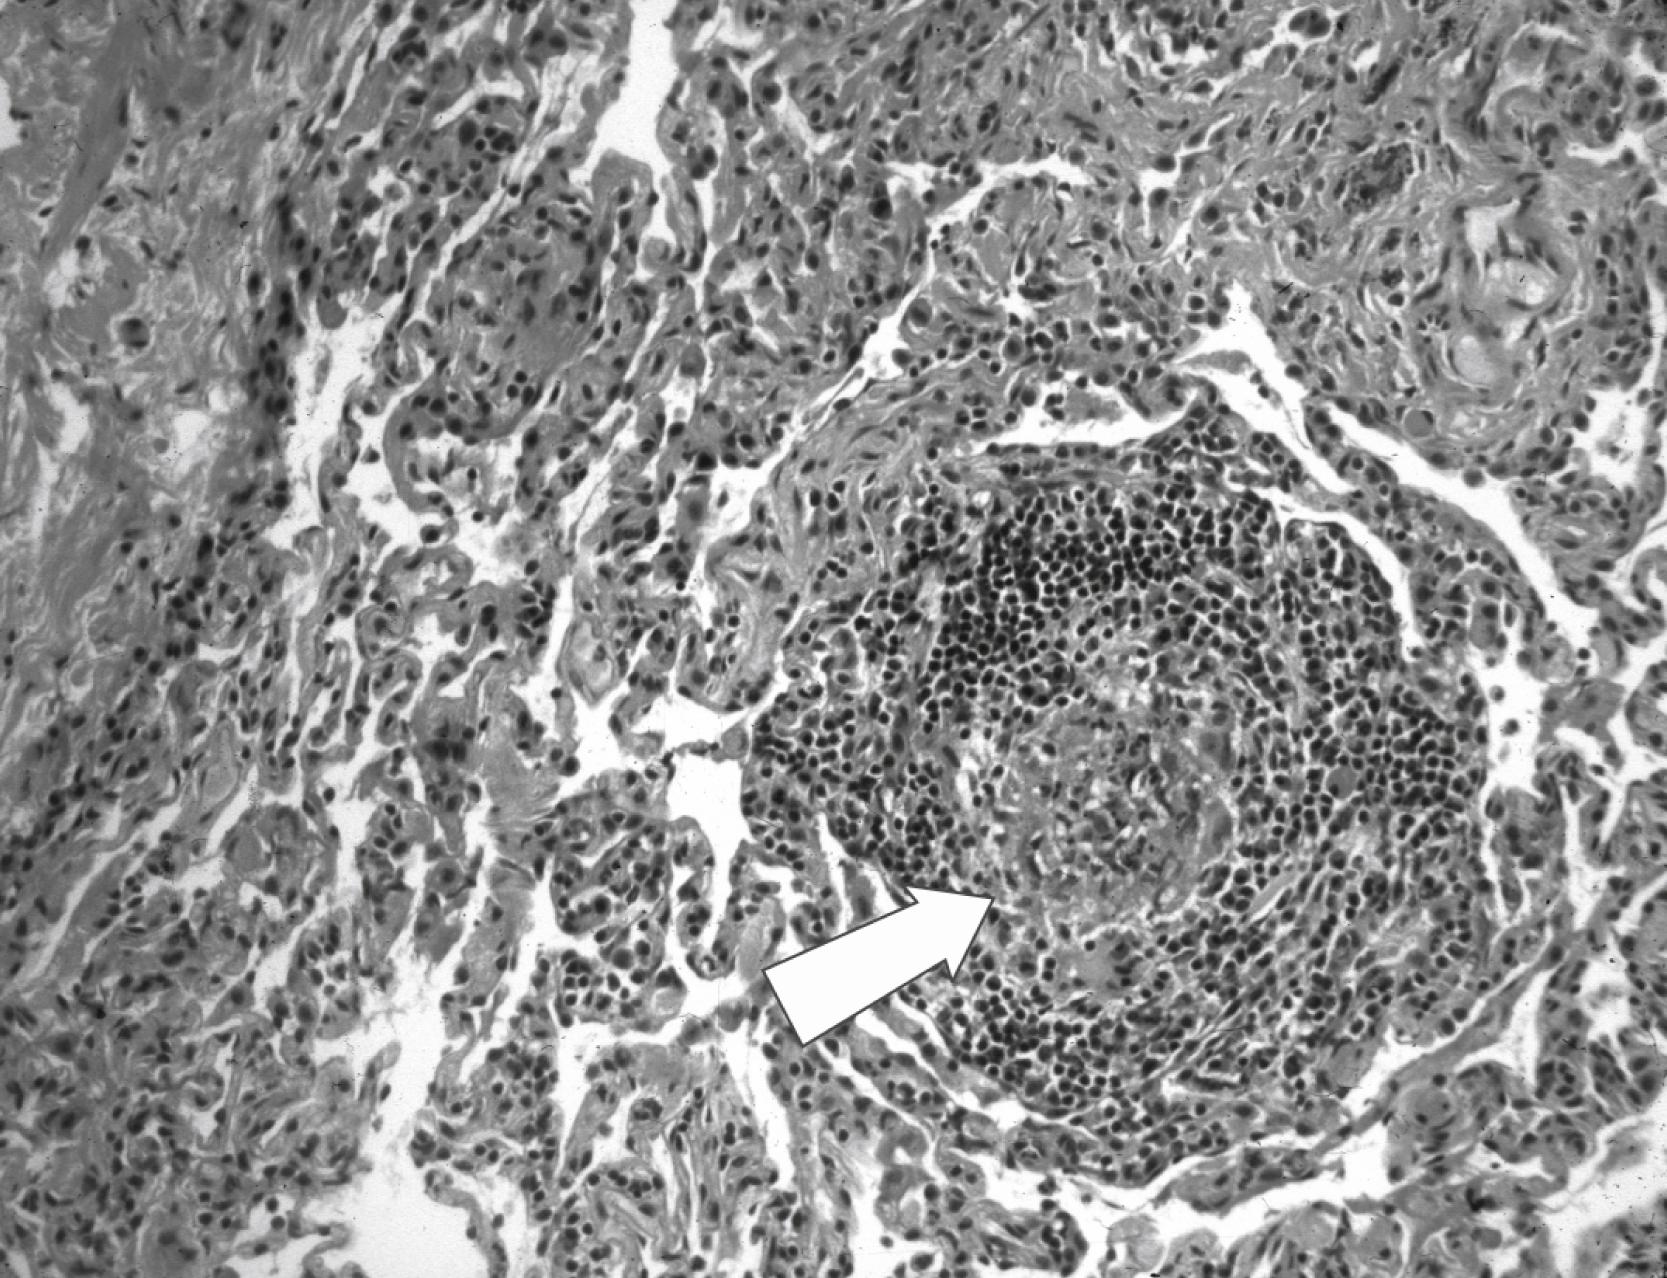

Abnormal acute inflammatory responses contribute to ineffective wound healing that is characteristic of these conditions. At sites of injury, histologic examination can show disordered inflammatory responses, such as combinations of acute and chronic inflammation ( Fig. 104.1 ) or poor accumulation of inflammatory cells. In some instances, abnormal inflammatory responses—rather than infection—are the major cause of pathology.

FIGURE 104.1, Pyogranuloma (acute inflammatory cells within granulomatous inflammatory response) (arrow) in the lung of patient with chronic granulomatous disease and Aspergillus spp. pneumonia.